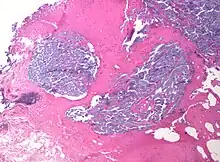

In medicine, desmoplasia is the growth of fibrous connective tissue.[1] It is also called a desmoplastic reaction to emphasize that it is secondary to an insult. Desmoplasia may occur around a neoplasm, causing dense fibrosis around the tumor,[1] or scar tissue (adhesions) within the abdomen after abdominal surgery.[1]

Desmoplasia is usually only associated with malignant neoplasms, which can evoke a fibrotic response invading healthy tissue. Invasive ductal carcinomas of the breast often have a stellate appearance caused by desmoplastic formations.

Desmoplasia refers to growth of dense connective tissue or stroma.[2] This growth is characterized by low cellularity with hyalinized or sclerotic stroma and disorganized blood vessel infiltration.[3] This growth is called a desmoplastic response and occurs as result of injury or neoplasia.[2] This response is coupled with malignancy in non-cutaneous neoplasias, and with benign or malignant tumors if associated with cutaneous pathologies.[3]